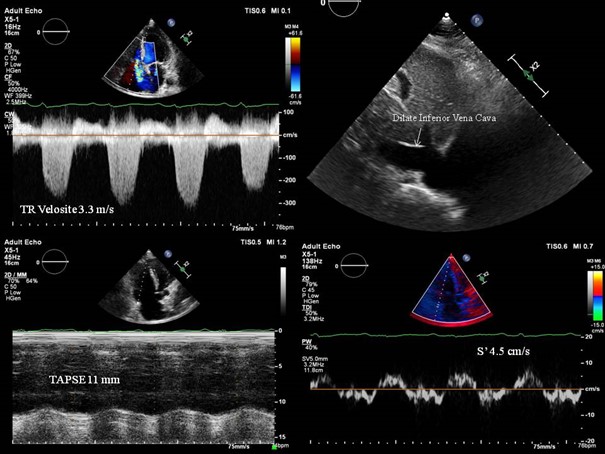

Yapılan transtorasik ekokardiyografide; Ejeksiyon fraksiyonu (EF) %45, sol ventrikül  inferior duvar bazalinde hipokinezi, hafif mitral yetmezliği saptandı. Sağ kalp fonksiyonları değerlendirildiğinde, ciddi triküspit yetmezliği üzerinden ölçülen triküspit velosite 3.3 m/sn (Video1), beraberinde dilate vena cava inferior (21 mm ve %50 altında kollobe oluyor) ve belirgin sağ kalp boşluklarında dilatasyon görüldü. (Resim 2, Video 2) Tahmini sistolik pulmoner arter basıncı 44+20 mmHg hesaplandı. Triküspit anülüsün sistolde apikale yer değiştirmesi (TAPSE, triküspid annular plane systolic excursion) 11 mm ve  doku Doppler görüntüleme (TDI, tissue Doppler imaging) S 4.5 cm/sn ölçülerek belirgin sağ kalp sistolik fonksiyonlarının azaldığı izlendi.(Resim 2)

Resim 2